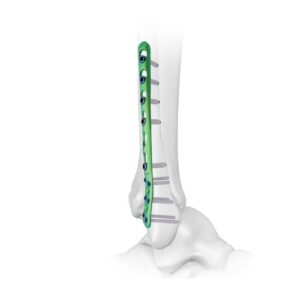

CLAVO PARA ARTRODESIS DE TOBILLO

El clavo para artrodesis de tobillo está diseñado para deformidades y artritis graves del pie y el tobillo.